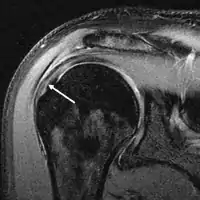

MRI

MRI of rotator cuff full-thickness tear

Magnetic resonance imaging (MRI) and ultrasound[47] are comparable in efficacy and helpful in diagnosis, although both have a false positive rate of 15–20%.[48] MRI can reliably detect most full-thickness tears, although very small pinpoint tears may be missed. In such situations, an MRI combined with an injection of contrast material, an MR-arthrogram, may help to confirm the diagnosis. It should be realized that a normal MRI cannot fully rule out a small tear (a false negative) while partial-thickness tears are not as reliably detected.[49] While MRI is sensitive in identifying tendon degeneration (tendinopathy), it may not reliably distinguish between a degenerative tendon and a partially torn tendon. Again, magnetic resonance arthrography can improve the differentiation.[49] An overall sensitivity of 91% (9% false negative rate) has been reported, indicating that magnetic resonance arthrography is reliable in the detection of partial-thickness rotator cuff tears.[49] However, its routine use is not advised, since it involves entering the joint with a needle, with the potential risk of infection. Consequently, the test is reserved for cases in which the diagnosis remains unclear.